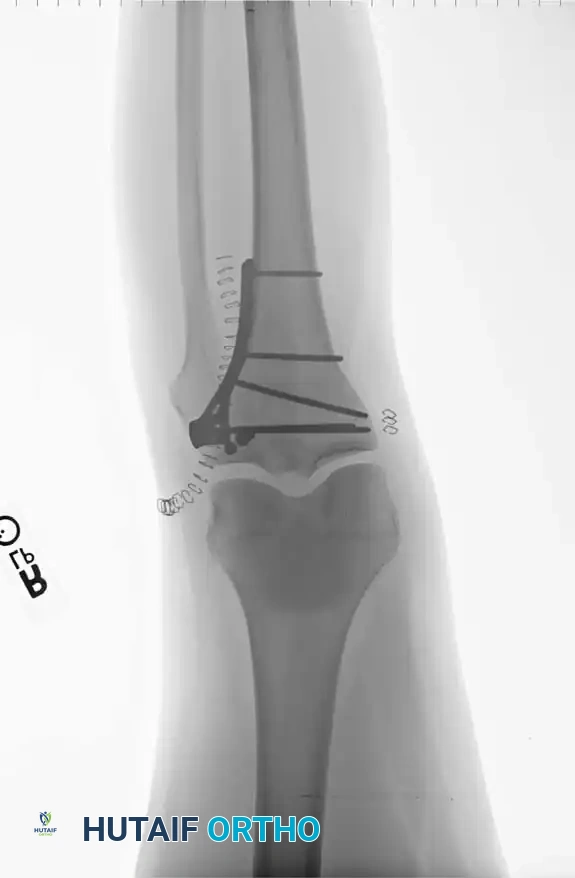

ثالثا استراتيجيات التثبيت الداخلي

بعد إعادة بناء سطح المفصل، يتم تثبيته بشكل نهائي باستخدام مسامير وشرائح معدنية مصممة خصيصا لتلائم شكل عظمة الساق العلوية.

تثبيت الكسر باستخدام الشرائح والمسامير

في الكسور المعقدة التي تشمل جانبي الركبة، غالبا ما يتطلب الأمر استخدام شريحتين معدنيتين لضمان عدم انهيار العظم تحت تأثير وزن الجسم.

استخدام شريحتين لتثبيت الكسور المعقدة

يقوم الجراح باستخدام جهاز الأشعة التداخلية للتأكد من استعادة المحور الميكانيكي للساق، والتأكد من عدم اختراق أي مسامير لسطح المفصل.

التصوير الإشعاعي أثناء الجراحة للتأكد من التثبيت